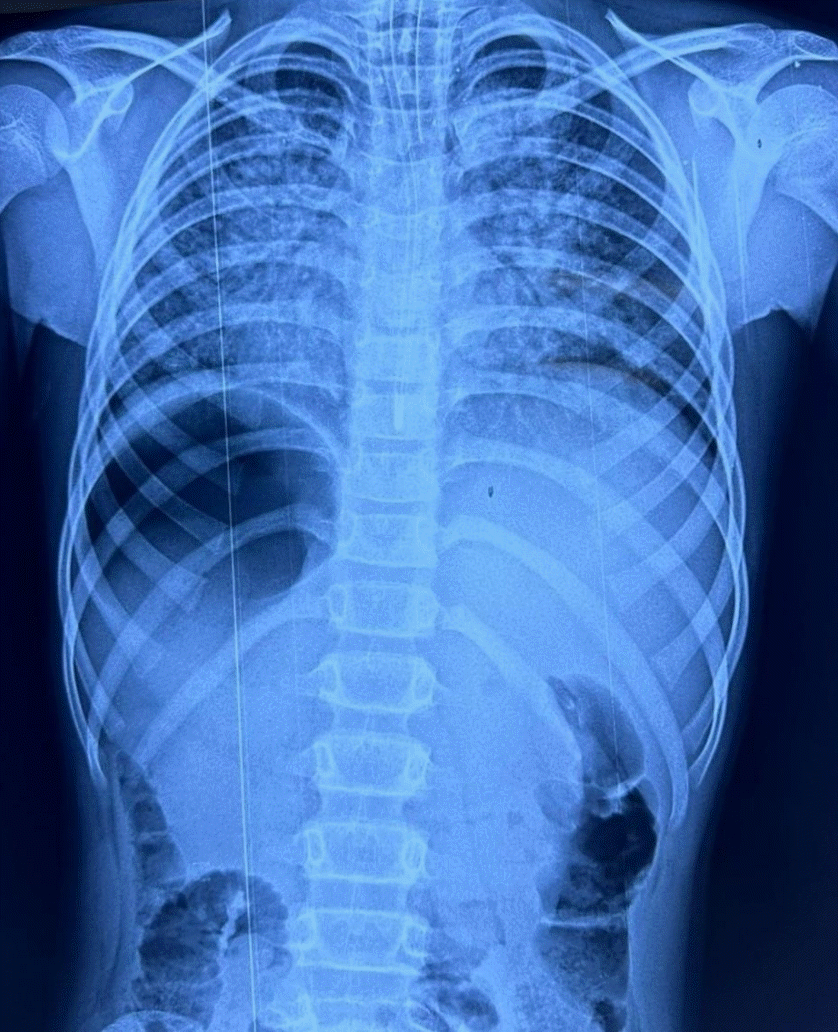

The initial chest radiograph showed the presence of pulmonary edema (Fig. 1). A blood gas analysis showed a severe respiratory and metabolic acidosis with pH 7.10, bicarbonate of 24.3 mmol/L, carbon dioxide of 89 mmHg, base deficit of 0.3 mmol/L, and lactate of 1.2 mmol/L. Primary laboratory tests showed normal electrolyte concentrations with no evidence of sepsis or multiorgan dysfunction. Within the first hour of hospitalization, his mental and respiratory statuses deteriorated to a Glasgow Coma Scale of 6 and type 2 respiratory failure, leading to endotracheal intubation, mechanical ventilation, and subsequent transfer to the pediatric intensive care unit.